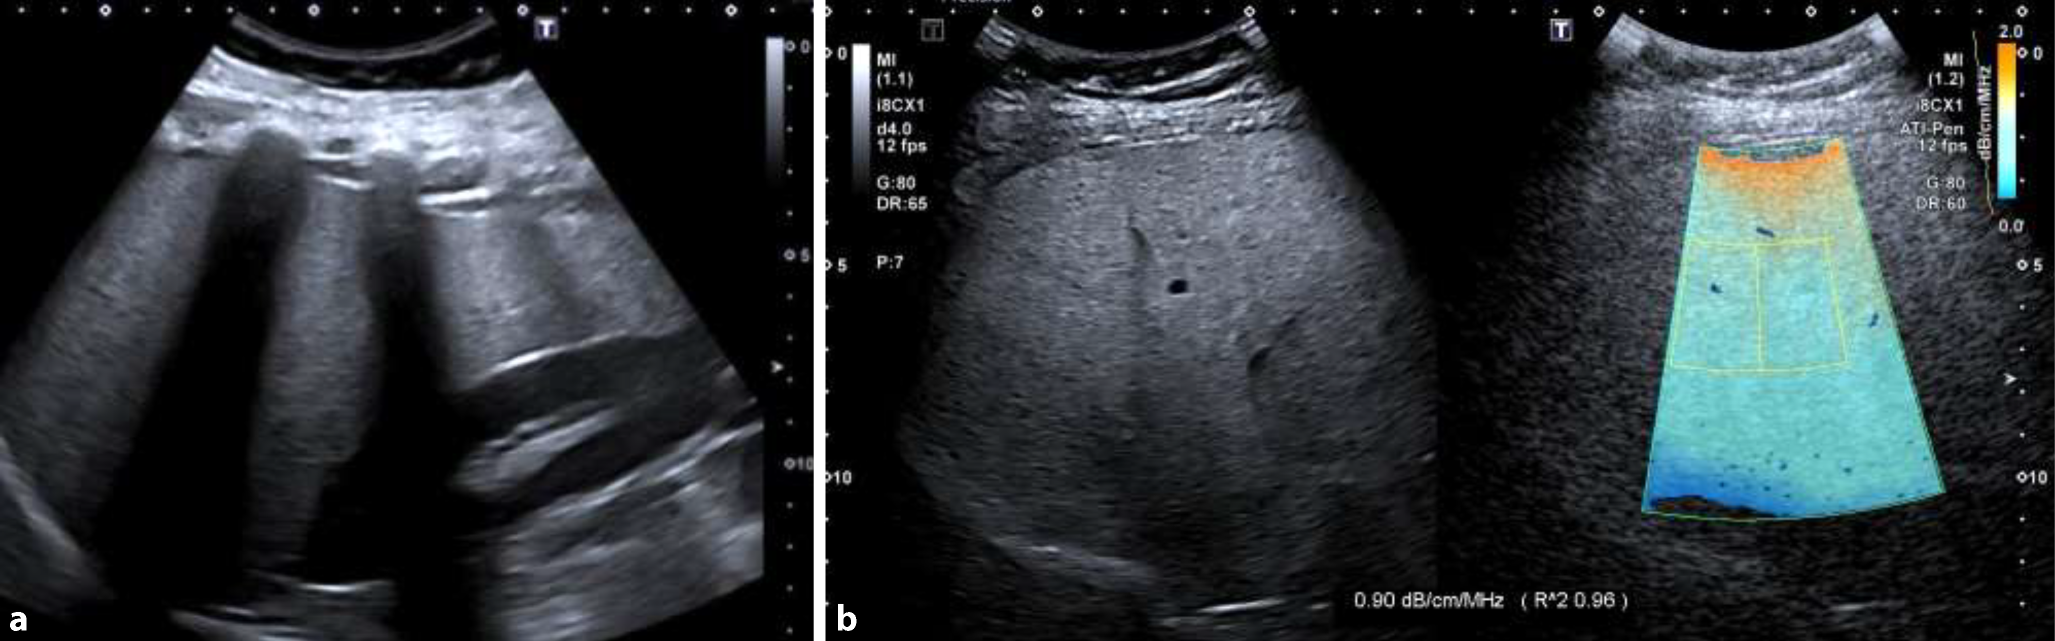

Laut der S2k-Leitlinie der Deutschen Gesellschaft für Gastroenterologie, Verdauungs- und Stoffwechselkrankheiten (DGVS) – sollen Kinder mit Adipositas (BMI > 97.P oder BMI > 90.P ± Risikofaktor) ab dem Alter von 8 Jahren mithilfe der Bestimmung der Alanin-Aminotransferase (ALT) für eine MASLD gescreent werden [14]. Nach Empfehlung der Nordamerikanischen Gesellschaft für Kindergastroenterologie (NASPGHAN) werden für Jungen ein ALT-Wert26IU/l und Mädchen22IU/l als Grenzwerte empfohlen [15]. Zur Diagnosestellung einer MASLD wird neben dem Vorliegen von kardiometabolischen Risikofaktoren der Nachweis einer Lebersteatose durch eine bildgebende oder histologische Untersuchung gefordert. Hierfür eignet sich im klinischen Alltag vorrangig die Abdomensonographie (Abb. 1a,b). Die weitreichende Verfügbarkeit, der Kostenfaktor, die schmerzfreie und schnelle Einschätzung über entweder die „Helligkeit“ des Leberparenchyms gegenüber der Niere/Milz oder mithilfe etablierter Scoring-Tools sind klare Argumente für einen ultraschallbasierten Nachweis einer Steatose. Sonographische Kriterien sind eine Organvergrößerung mit glatter Oberfläche, ein stumpfwinkeliger kaudaler Rand, die erhöhte Echogenität, meist homogene Echotextur, die verminderte Schallleitung und Rarefizierung der Lebervenen. Erschwert werden kann die Diagnose bei der Adipositas durch die Schallabschwächung aufgrund der verdickten Bauchdecke [16].

Abb. 1

a,b Sonographische Darstellung einer Metabolische-Dysfunktion-assoziierten Steatohepatitis und Scherwellenelastographie der Leber. Fall: 10-jähriger Junge mit Adipositas (BMI 33,5 kg/m2) und ausgeprägter Steatohepatitis. Glutamat-Pyruvat-Transaminase (ALT, alanin aminotransferase) 232 U/l, Glutamat-Oxalacetat-Transaminase (AST, aspartat aminotransferase) 160 U/l. Histologisch: mikrovesikuläre Steatose (ca. 90 %) und Leberfibrose Grad II. Sonographisch deutliche Echogenitätserhöhung des Leberparenchyms mit starkem Echogenitätskontrast zur Niere. Das Attenuation Imaging zeigt einen deutlich erhöhten Leberdämpfungsquotienten von 0,90 dB/cm/MHz. Mit freundl. Genehmigung von Dr. Benas Prusinskas, Universitätskinderklinik II, Essen